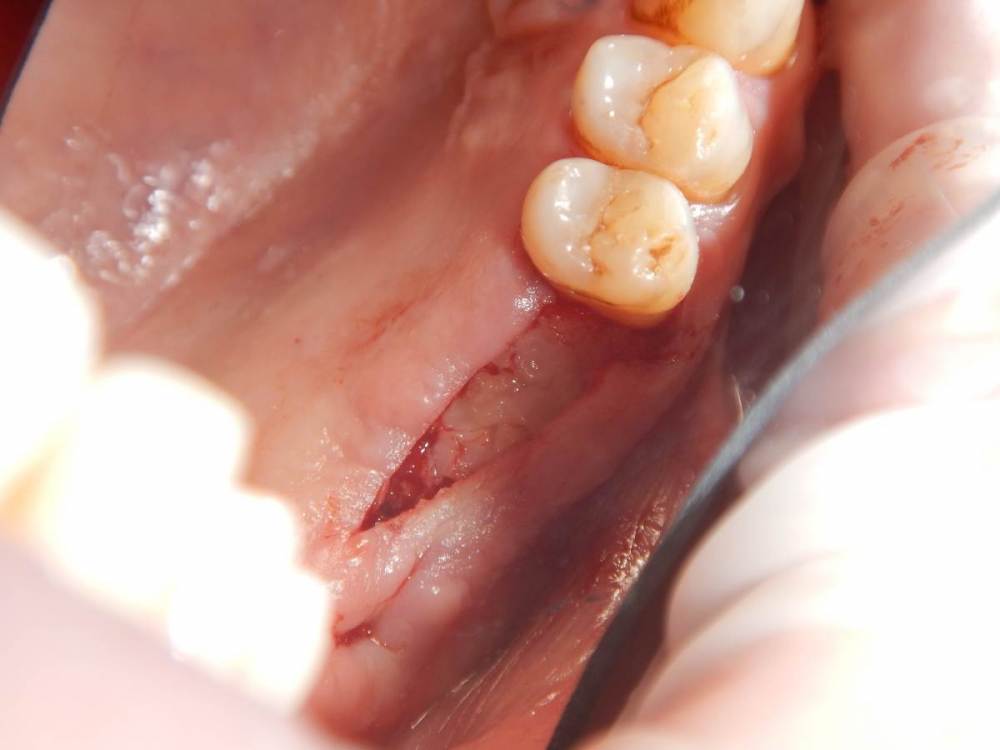

annda Опубликовано 12 июня, 2021 Автор Поделиться Опубликовано 12 июня, 2021 (изменено) Спасибо всем. Вмешательства не было, кроме удаления. Я так понимаю, тактика заключается в доступе и банально кюретаже? Графт по убеждениям, дефект все одно получается практически четырехстеночный... Главное, не наджабить кортикалку ГП. Я так понимаю, процесс все же из пазухи, был с зубами связан? Изменено 12 июня, 2021 пользователем annda Ссылка на комментарий

Astronaft Опубликовано 12 июня, 2021 Поделиться Опубликовано 12 июня, 2021 (изменено) В моем случае процесс одонтогенный. Киста это остаток после удаления зуба. В вашем случае не должен быть из пазухи. Да - там есть истончение кортикальной пластины в одном месте, но вроде как без инвагинации. Границы везде четкие, т.е. процесс доброкачественный. Из пазухи в кость можно проникнуть только инвазивно. Лизис, а не раздвигание. Карцинома - границы были бы другие. Т.е. процесс либо происходит из самой кости, или одонтогенный. Изменено 12 июня, 2021 пользователем Astronaft 1 Ссылка на комментарий

annda Опубликовано 18 июня, 2021 Автор Поделиться Опубликовано 18 июня, 2021 Он про остеиндукцию процесса из пазухи сказал. Про недоразвитие этой пазухи. Ссылка на комментарий